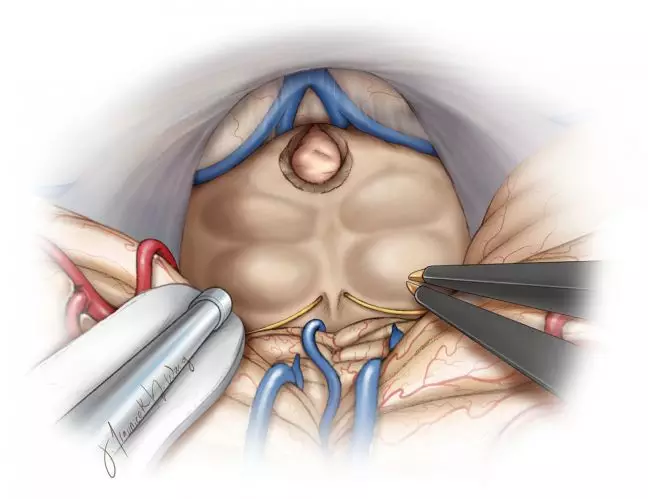

图8. 患者取坐位,通过后正中小脑上入路显露图2显示的肿瘤。注意左侧顶盖的颜色差异(左图,吸引器顶端)。切除侵及顶盖部分后才可进入脑室并全切除肿瘤(右图)。